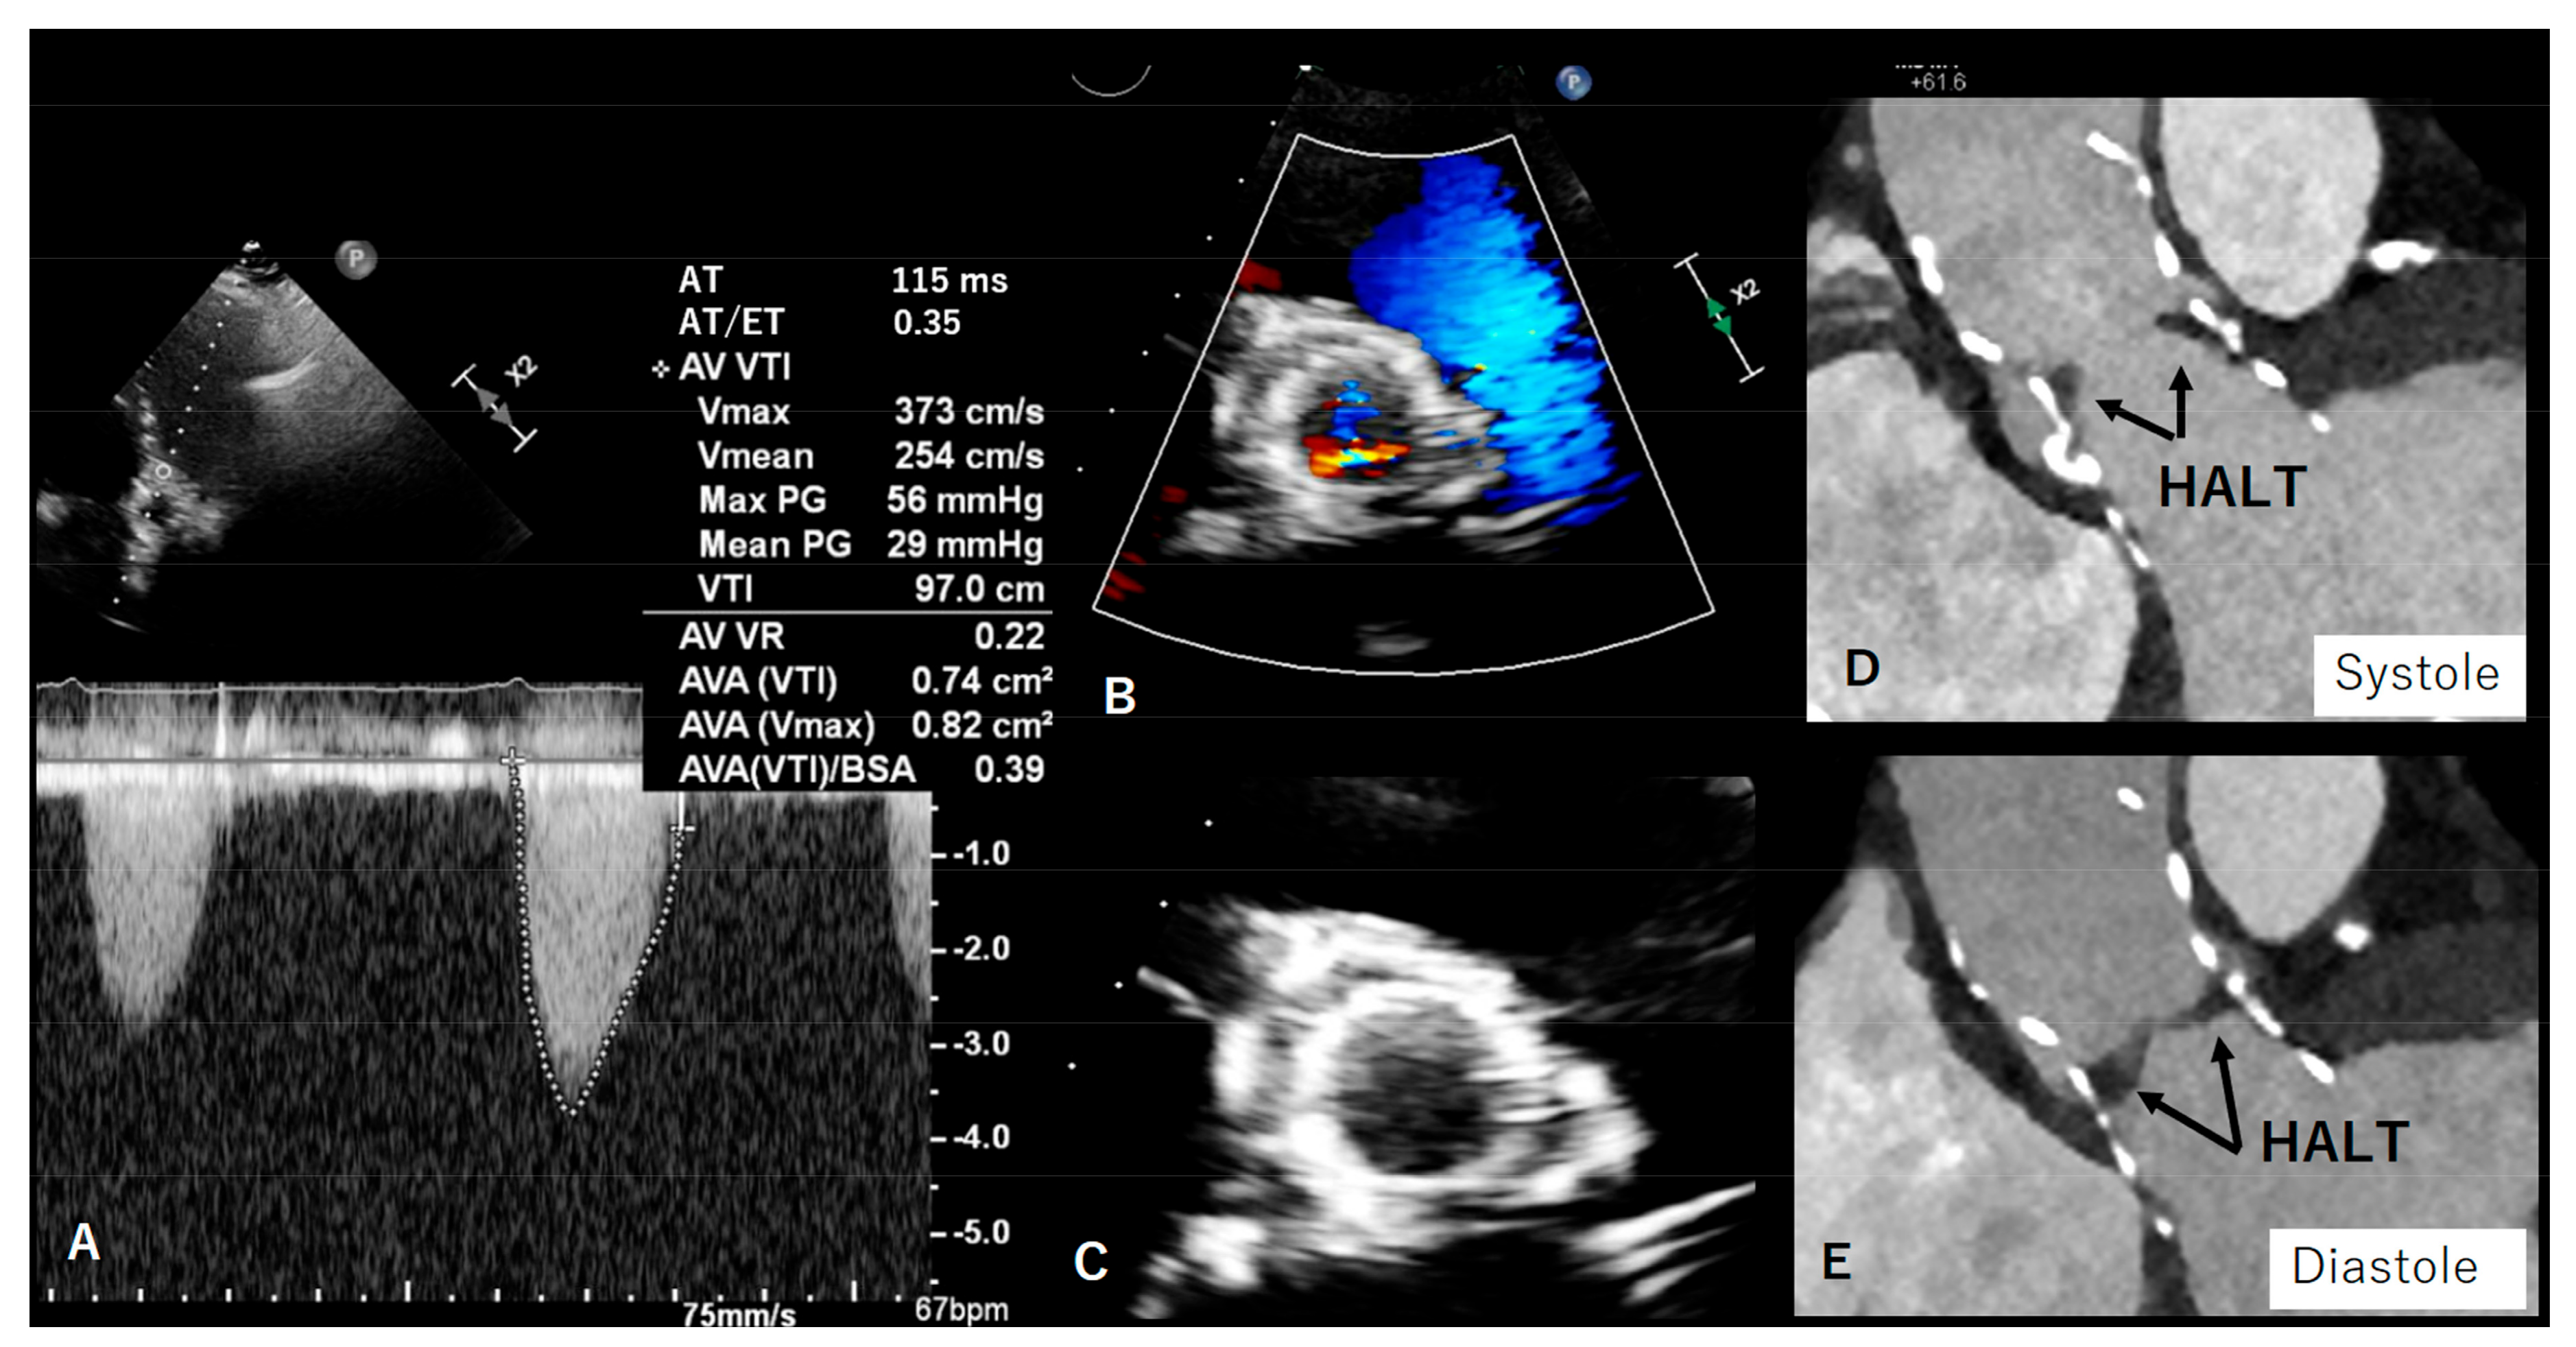

4. Valve Thrombosis/HALT/Pannus